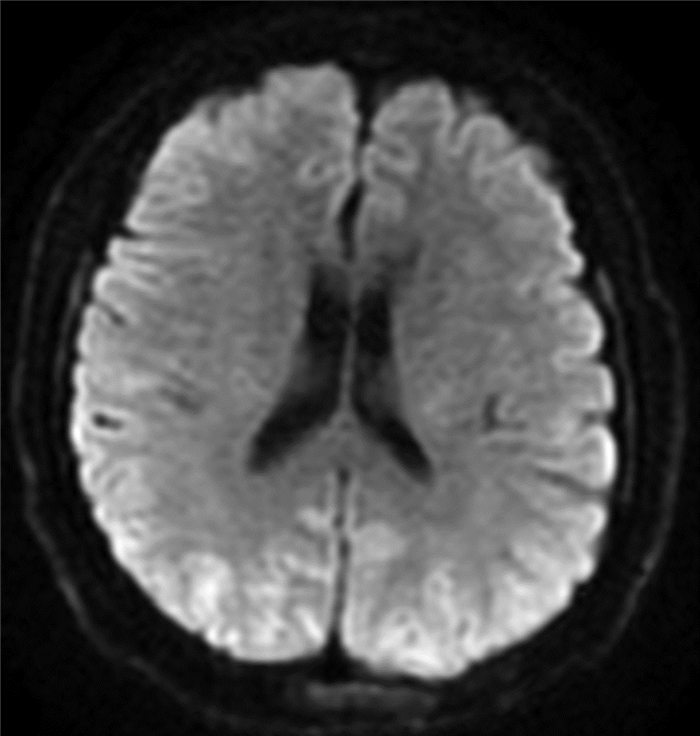

Endoscopic treatment of gastroesophageal varices complicated by posterior reversible encephalopathy syndrome: A case report

Tingting YU, Shanshan JIANG, Mengran ZHU, Yun BAI

2022, 38(1): 177-179. DOI: 10.3969/j.issn.1001-5256.2022.01.030

Abstract(807) HTML (197) PDF (3069KB)(54)

Abstract: